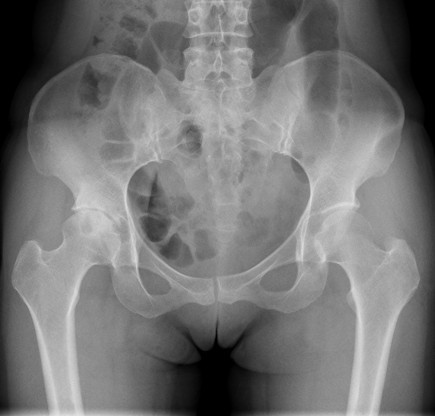

查体:右髋部软组织未见肿胀,双下肢皮肤无破溃,双足趾间皮肤干燥、完好。右髋部后侧轻压痛,双侧足背动脉和胫后动脉搏动正常。 辅查:X线:双侧侧髋臼较浅,髋臼外上方软骨下骨硬化及骨赘,Sharp角右侧约48°、左侧约50°,CE角右侧约20°、左侧约18°,右侧髋关节间隙狭窄,右侧髋臼、股骨头可见囊性改变。

诊断: 1.右侧髋关节发育不良骨关节炎(crowe I型) 2.左侧髋关节发育不良(crowe I型) 3.上呼吸道感染 治疗:排除手术禁忌症后择期手术治疗。